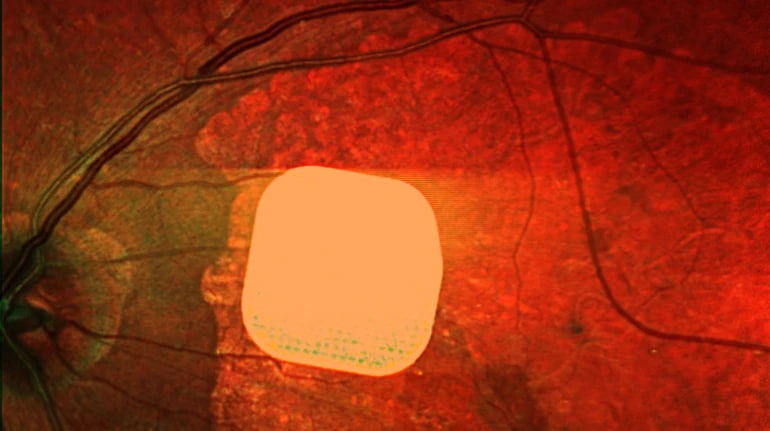

Британські лікарі з лондонської клініки Moorfields Eye Hospital разом із колегами з інших європейських медзакладів випробували новий електронний імплант Prima, який допомагає частково відновити зір пацієнтам із макулодистрофією – хворобою, що призводить до втрати зору після 50 років. Цей мікрочип, розміром лише 2×2 міліметри, встановлюють під сітківку ока, а пацієнту також під’єднують систему окулярів доповненої реальності. Під час дослідження 38 пацієнтів із важкою втратою зору після імплантації імпланту Prima змогли розрізняти літери, цифри та слова. Лікарі вважають, що ця технологія відкриває нові можливості для людей із серйозними зоровими проблемами, дозволяючи покращити їх якість життя.